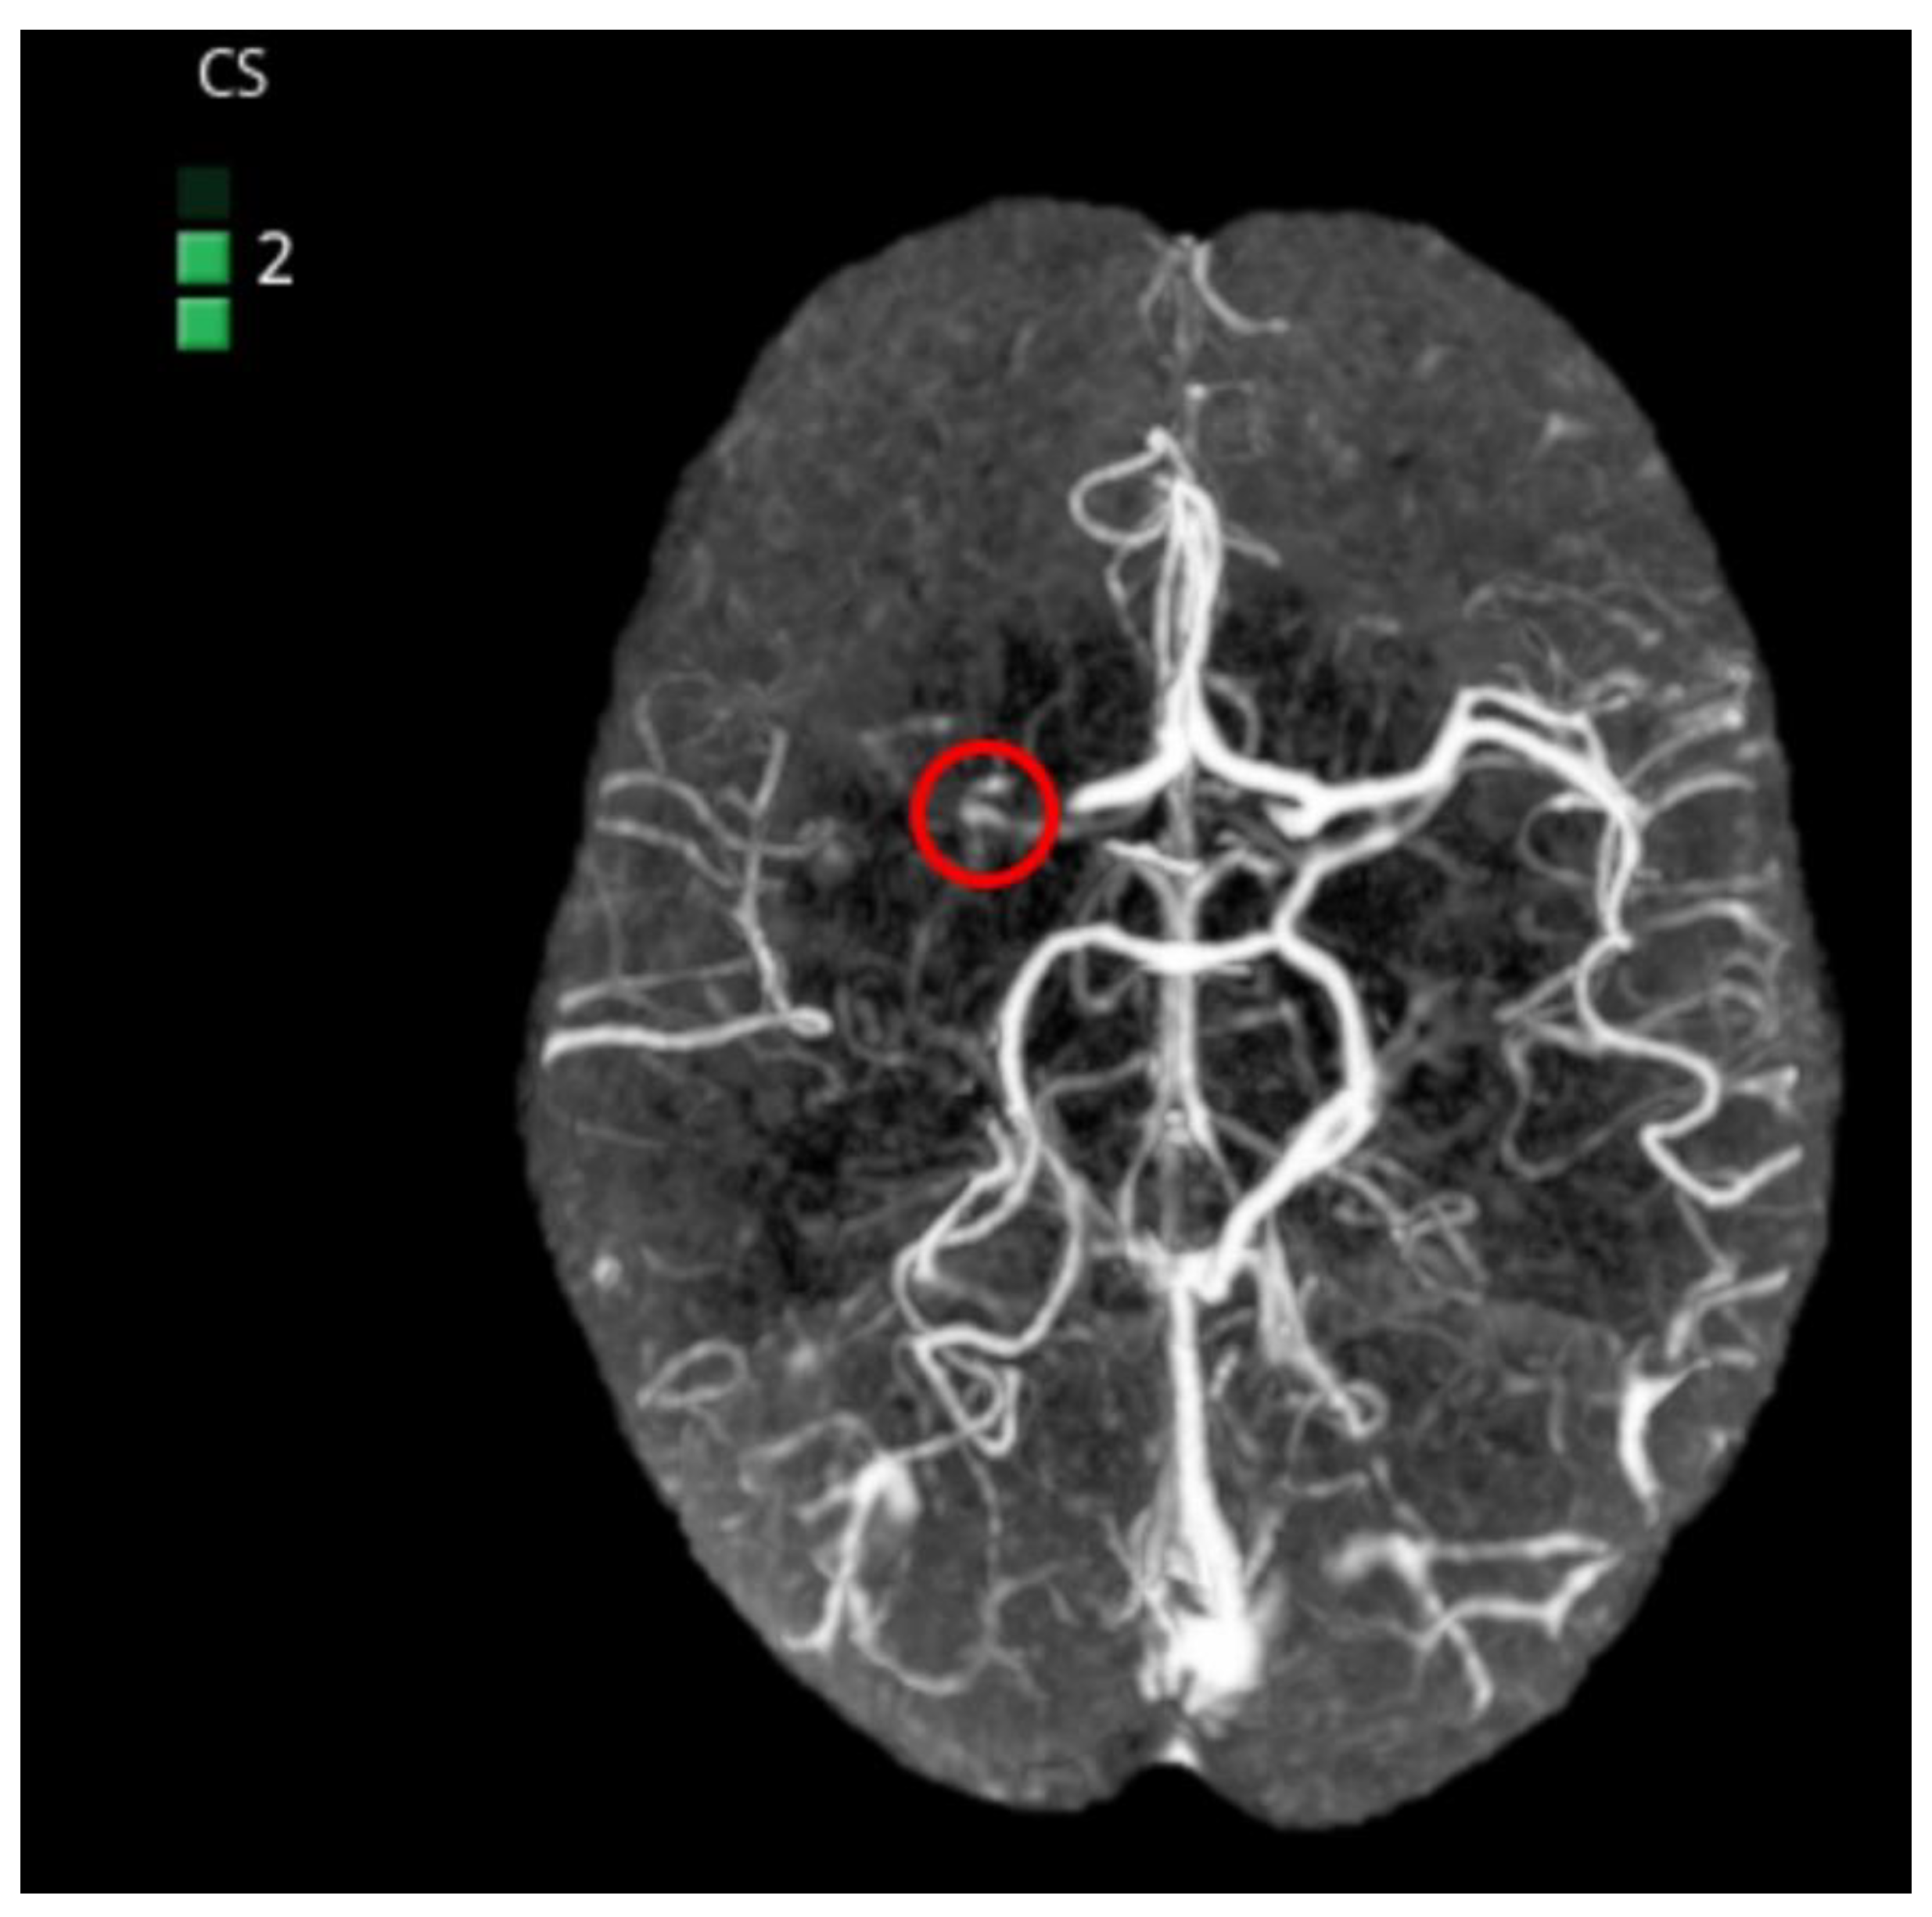

Artery Occlusion Detection